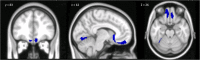

In recent years, structural and functional alterations in the cerebellum have been reported in autism spectrum disorder (ASD). Intriguingly, recent studies demonstrated that the social behavioral profile of individuals with cerebellar pathologies is characterized by a theory of mind (ToM) impairment, one of the main behavioral hallmarks of ASD. The aim of the present study was to compare ToM abilities and underlying cerebello-cortical structural patterns between ASD individuals and individuals with cerebellar atrophy to further specify the cerebellar role in mentalizing alterations in ASD. Twenty-one adults with ASD without language and intellectual impairments (based on DSM-5), 36 individuals affected by degenerative cerebellar damage (CB), and 67 healthy participants were enrolled in the study. ToM abilities were assessed using the reading the mind in the eyes test and the faux pas test. One-way ANCOVA was conducted to compare the performances between the two cohorts. Three-dimensional T1-weighted magnetic resonance scans were collected, and a voxel-based morphometry analysis was performed to characterize the brain structural alterations in the two cohorts. ASD and CB participants had comparable ToM performance with similar difficulties in both the tests. CB and ASD participants showed an overlapping pattern of gray matter (GM) reduction in a specific cerebellar portion (Crus-II). Our study provides the first direct comparison of ToM abilities between ASD and CB individuals, boosting the idea that specific cerebellar structural alterations impact the mentalizing process. The present findings open a new perspective for considering the cerebellum as a potential target for treatment implementation. The present work will critically advance current knowledge about the cerebellar role in ToM alterations of ASD, in particular, elucidating the presence of common cerebellar structural abnormalities in ASD and cerebellar individuals that may underlie specific mentalizing alterations. These findings may pave the way for alternative therapeutic indications, such as cerebellar neuromodulation, with a strong clinical impact. LAY SUMMARY: The present work will critically advance current knowledge about the cerebellar role in theory of mind alterations of autism spectrum disorder (ASD), in particular, elucidating the presence of common cerebellar structural abnormalities in ASD and cerebellar individuals that may underlie specific mentalizing alterations. These findings may pave the way for alternative therapeutic indications, such as cerebellar neuromodulation, with a strong clinical impact.